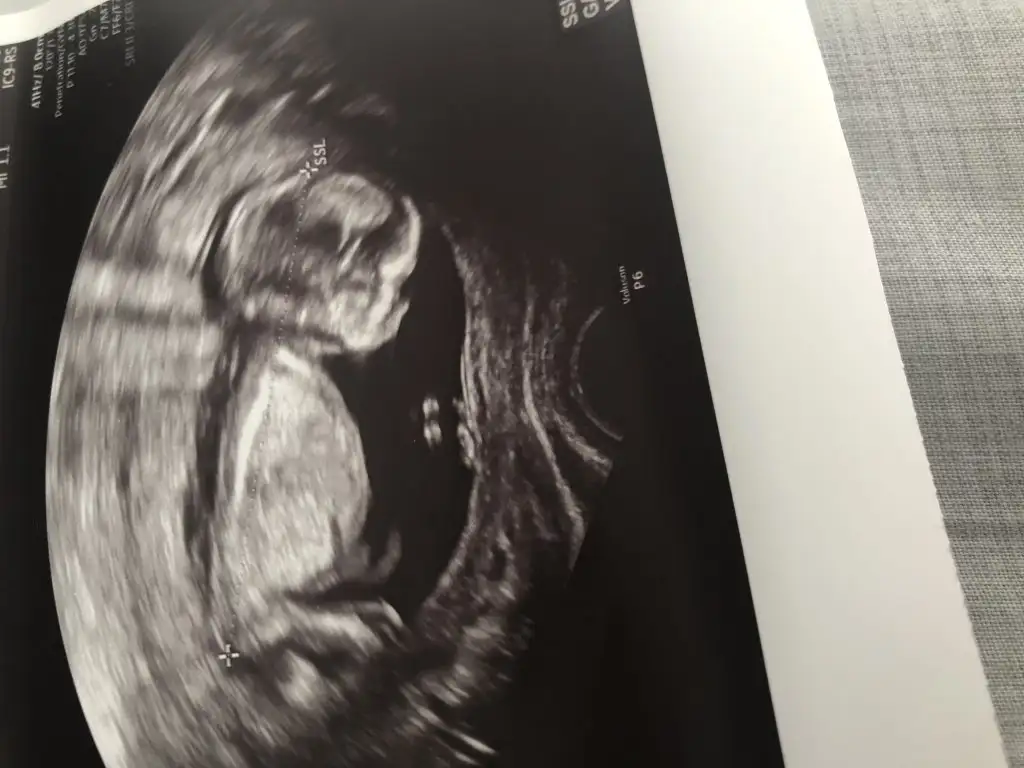

Tesekkur ettim canım saolun bakalım sonraki usglereErkek olduğunu düşünüyorum

Detaylıda ögrendinizmi ogluşmu geliyor hani dönmediniz anketimi oylicaktınızEvet ilk bebek ilk heyecanlarr5şubatta detaylı ultrason var heralde ozaman artık söyler görür doktor gerçi özeldeki 13ncü haftada erkek dedi bakalım şimdimi anketi yapıyım yoksa şubatta kesin sonuç olduğundamı tabi olursa

Dr tahminde bulunmadımı 15+3 haftadasınız

Erkek dedi tam emin değilim dediDr tahminde bulunmadımı 15+3 haftadasınız

Evettt erkek geliyorrrrDetaylıda ögrendinizmi ogluşmu geliyor hani dönmediniz anketimi oylicaktınız

13 + olanda nubunu göremedim 15+ da görüntüsüne kız gibi dedim o nedenle 11 yada 12 yada 13 hafta usg istemiştim oda net degil dr ne zaman tahmin etti dr erkek dediyse dogrudur daha detaylı bakıyorErkek dedi tam emin değilim dedi

13 + olanda nubunu göremedim 15+ da görüntüsüne kız gibi dedim o nedenle 11 yada 12 yada 13 hafta usg istemiştim oda net degil dr ne zaman tahmin etti dr erkek dediyse dogrudur daha detaylı bakıyor